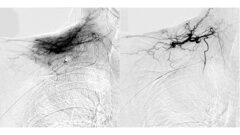

泌尿器の機能が正常な場合は、膀胱に尿がたまると大脳に尿意を伝える信号が送られます。この信号を伝える神経系の中核は大脳皮質にあり、脳幹部から「脊髄→腰にある仙髄→末梢神経」を経由して膀胱や尿道の排尿筋や括約筋につながっています。この神経系の情報伝達によって膀胱を収縮させる膀胱排尿筋や尿道を締める筋肉である尿道括約筋といった蓄尿・排尿に関わる筋群が作用し、スムーズな蓄尿・排尿が促されるのです。

導尿によって膀胱にたまった尿を排出し、残尿をなくすことで膀胱内圧を低く維持できます。その結果、排尿筋の線維化によって凹凸ができてしまう肉柱形成や、膀胱粘膜が膀胱壁の外に突出してしまう膀胱憩室を防ぐこともできるのです。